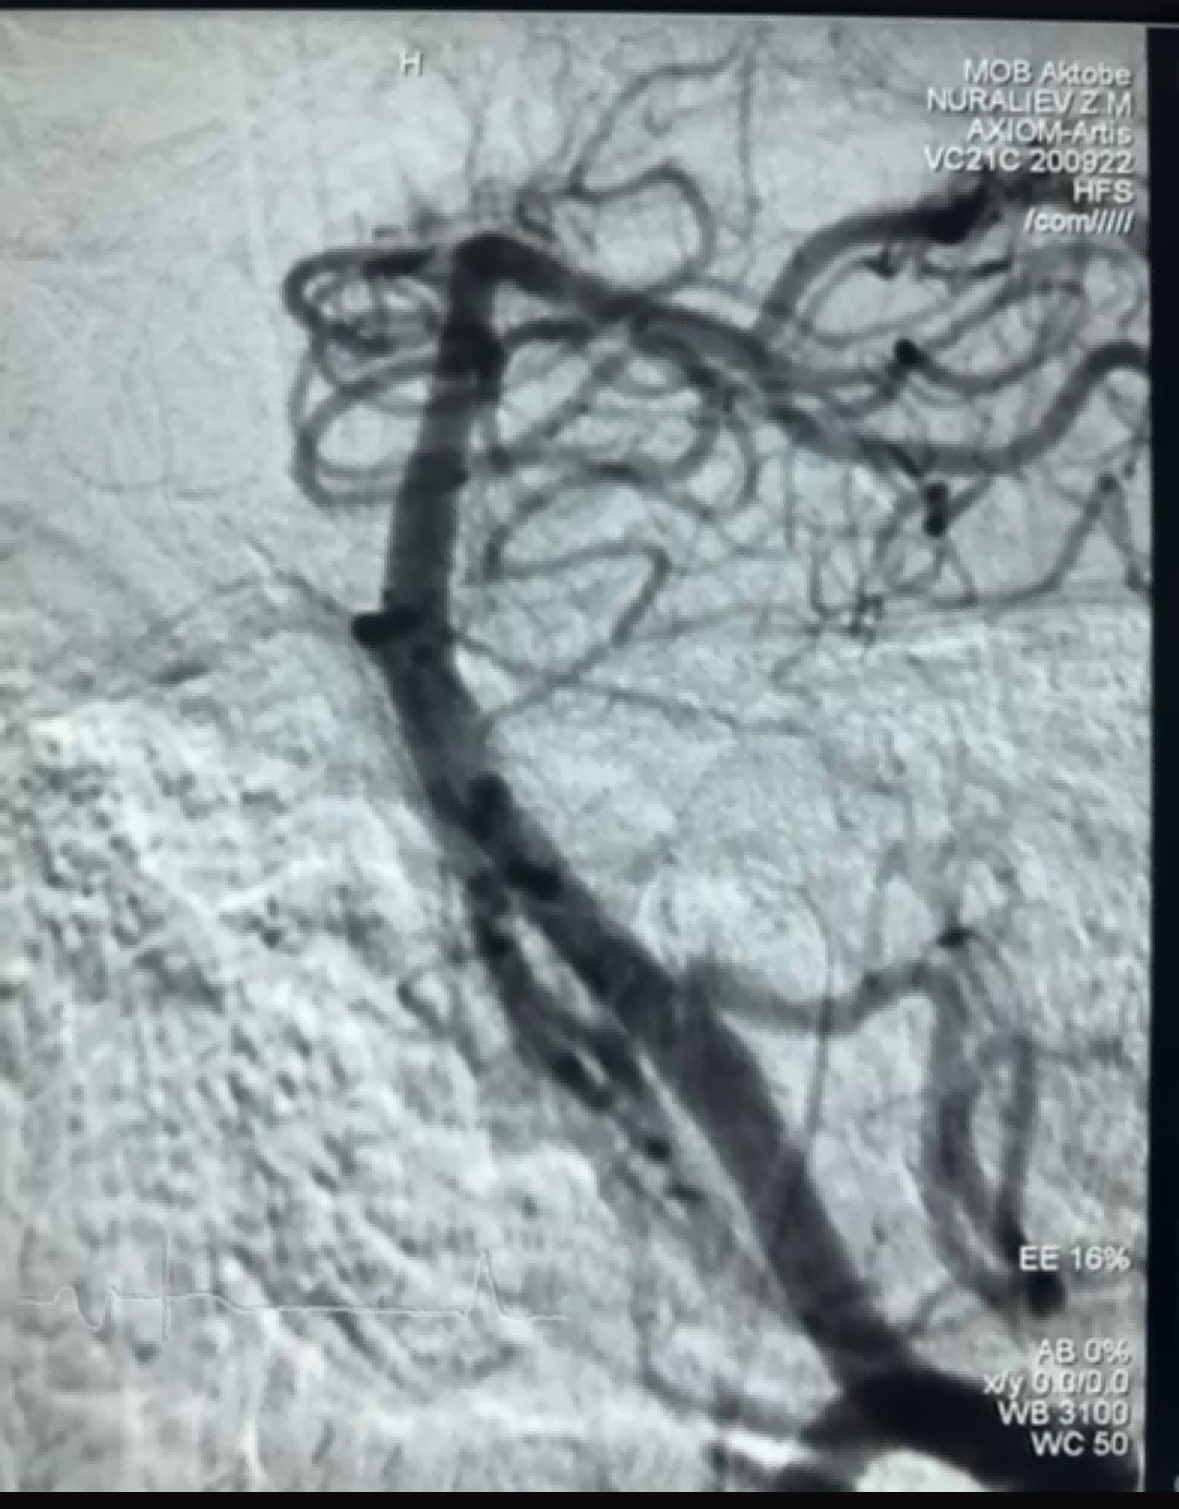

Recently, there was a successful thrombectomy case using the Dredger Stent Retriever of NeuroSafe Medical Co., Ltd. The Dredger Stent Retriever has a non-invasive soft tip, which greatly reduces the risk of intimal damage, and has a unique special-shaped hole design that captures blood clots mainly by clamping the gap changes.